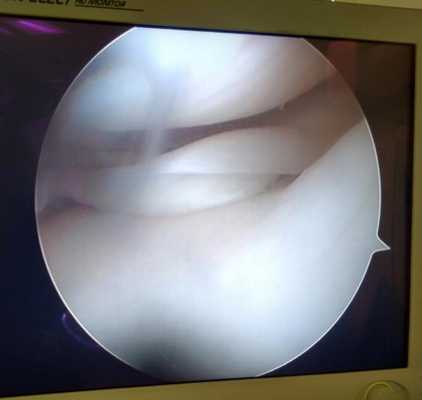

Удалённый фрагмент внутреннего мениска при разрыве по типу ручки лейки с блоком коленного сустава.

Мениск после обработки по поводу паракапсулярного субтотального разрыва по типу ручки лейки.